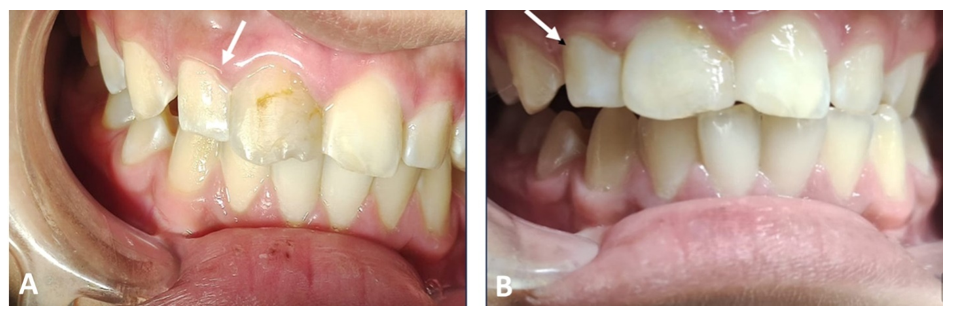

The patient did not report any painful symptoms during the 3-month rest treatment or at other follow-up visits. The case was clinically asymptomatic as all signs and symptoms had disappeared completely, and the gingiva appeared normal on follow‐up recall (Figure 3). Periapical radiographs show signs of healing of the periapical lesion, increasing radiopacity, and decreasing root divergence through follow‐up recall at 6, 12, and 18 months (Figure 4).

Figure 3 Clinical lateral views show the straightening of the tilted lateral incisor #12 (arrow) after two years (A) and complete treatment after restoration of the upper central incisor #11 (B).

After 24 months, follow-up radiographs showed up-righting of tilted roots and a decrease in radiolucency of the lesion, reflecting healing with new bone formation. The severe displacement was corrected, and the patient no longer required orthodontic treatment (Figure 5).